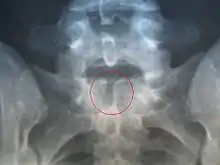

Розщеплення хребта

Розщеплення хребта (лат. Spina bifida) — дефект розвитку хребта, що полягає в аномальному розвитку хребта, яке викликане розщепленням — незакриттям хребетного каналу (іншими словами: відсутність задньої частини дуг хребців). Цей дефект виникає приблизно на 3-му тижні вагітності. Залежно від району залягання розрізняють грижі шийного, грудного, поперекового та крижового відділів. Добавки фолієвої кислоти під час вагітності зменшують ймовірність розвитку розщеплення хребта[2] .